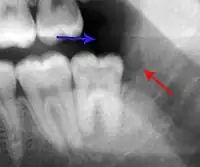

xray of pericoronitis

A radiograph (X-ray) of the above tooth showing chronic pericoronitis, operculum (blue arrow) and bone destruction (red arrow) from chronic inflammation. Tooth is slightly disto-angular.